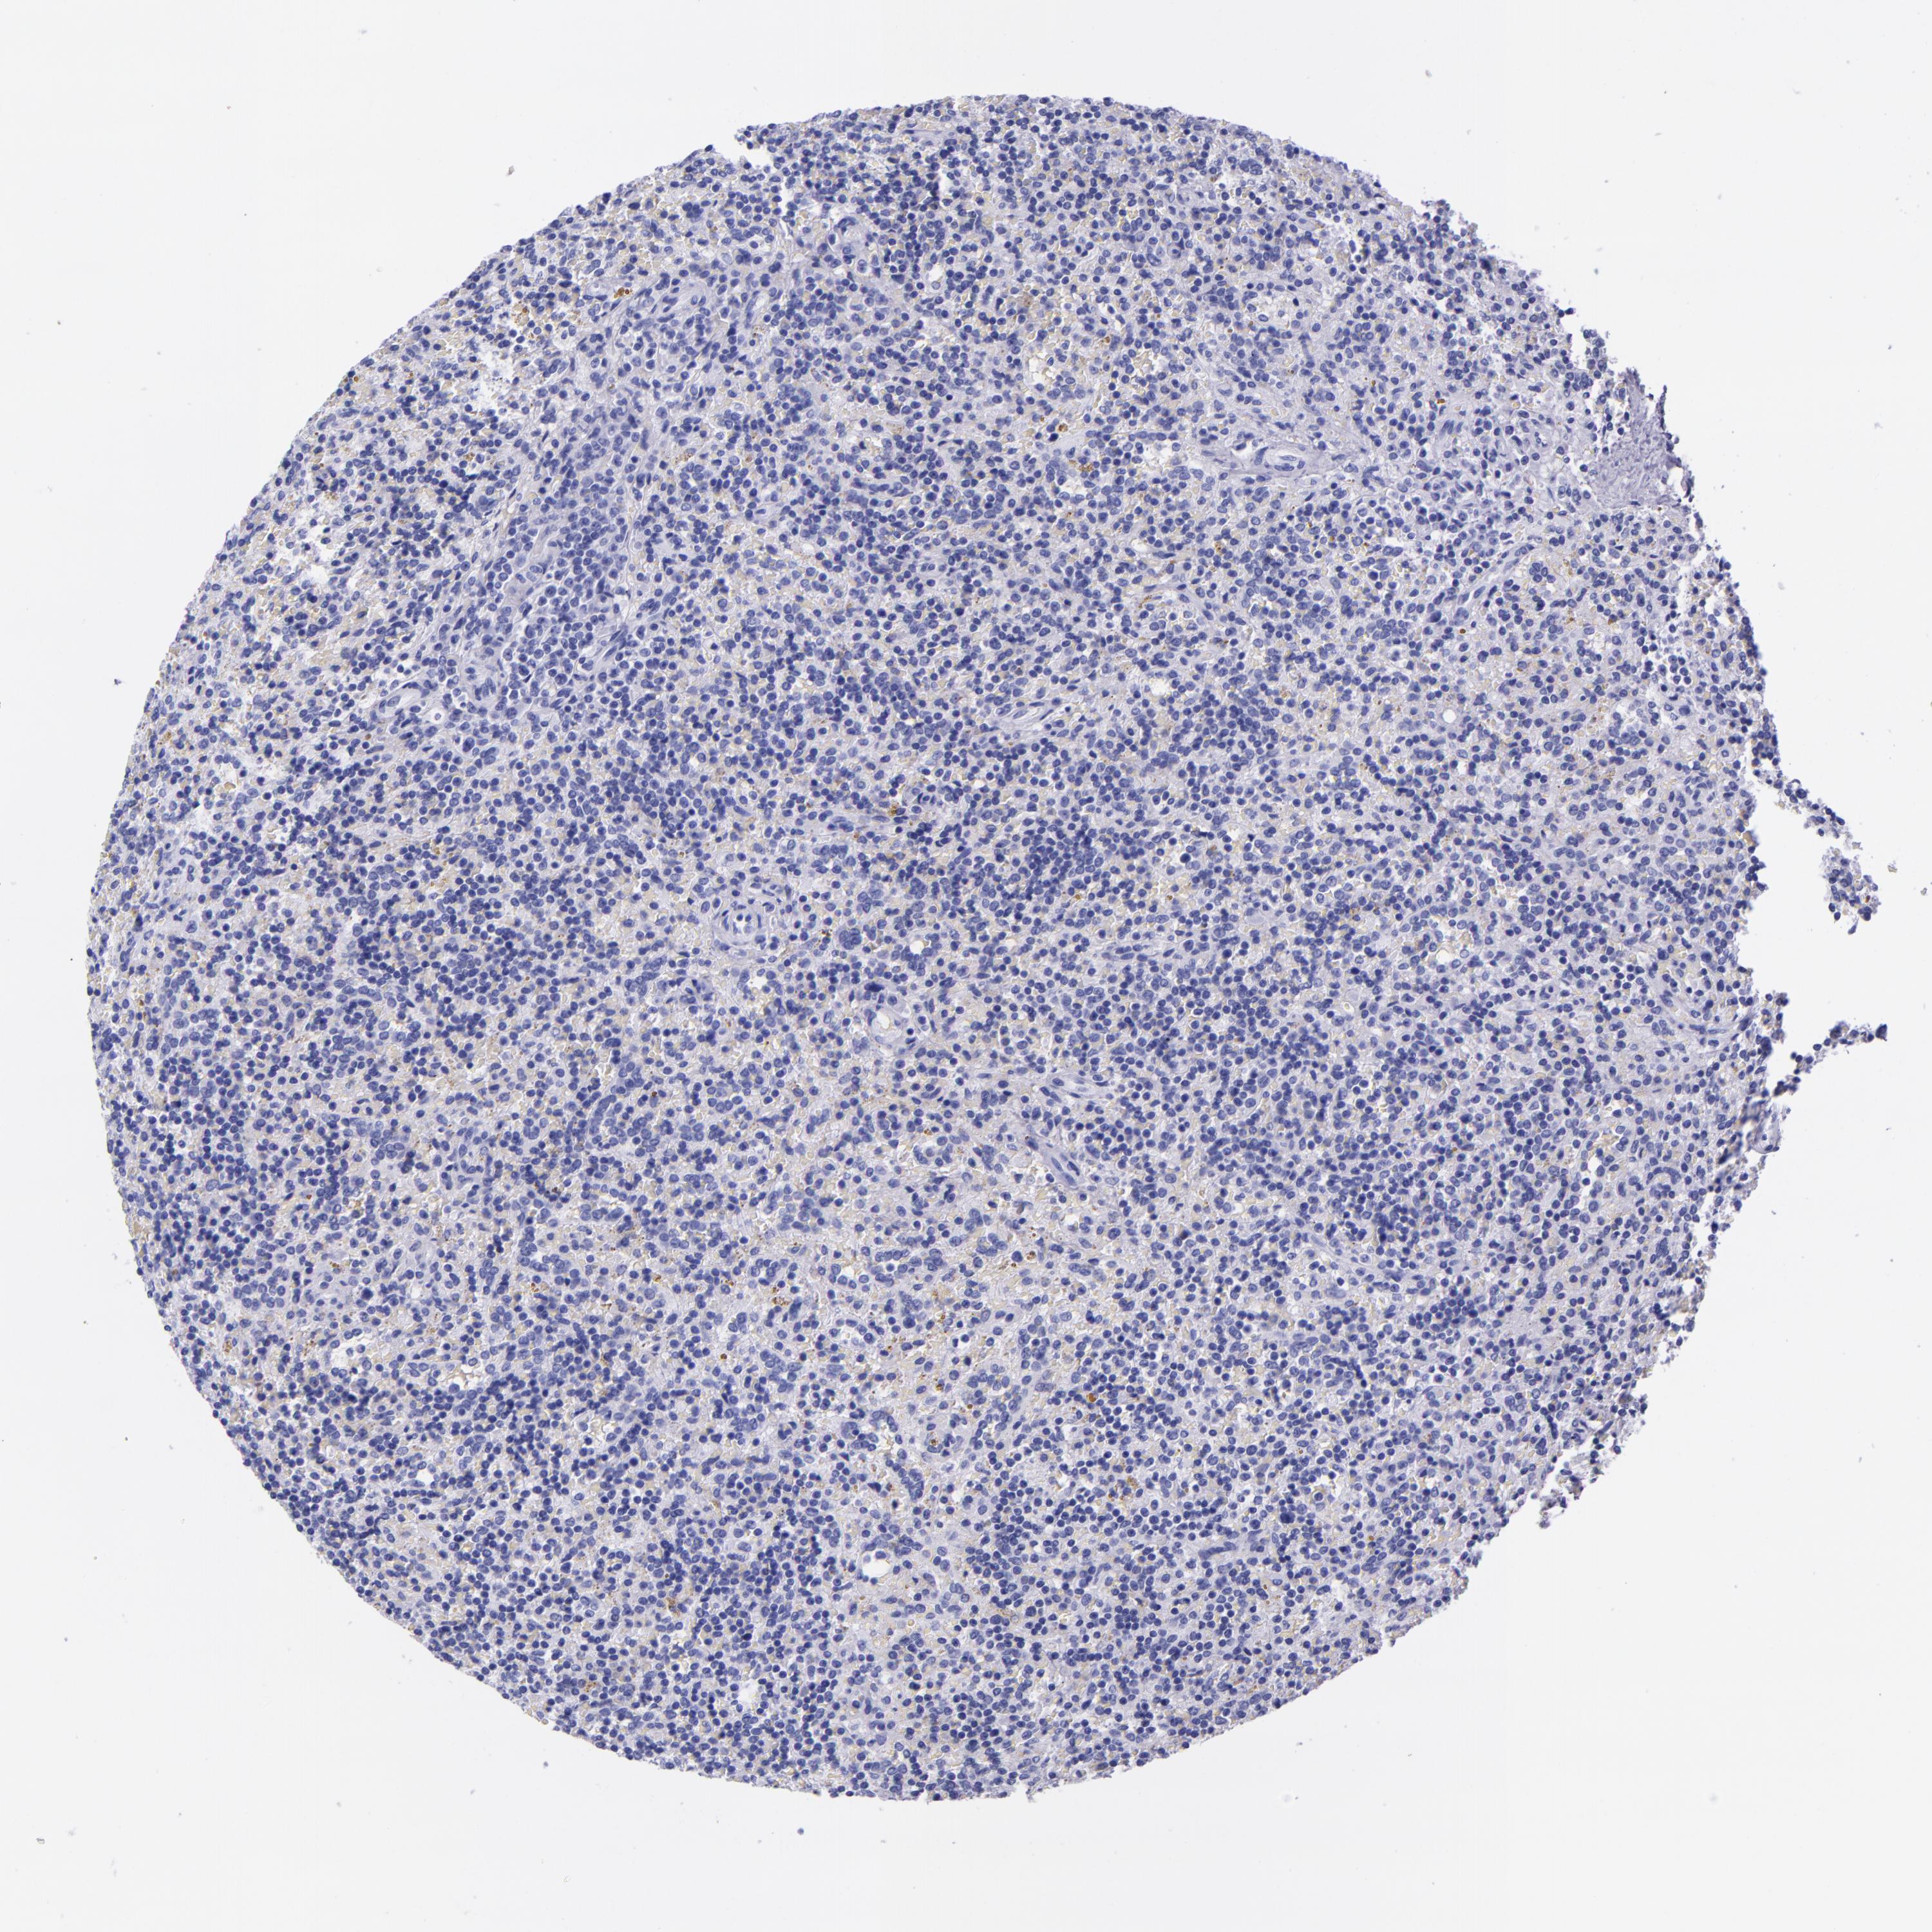

CANCER LYMPHOMA Show tissue menu

LYMPHOMA - Protein expressioni

A mouse-over function shows sample information and annotation data. Click on an image to view it in a full screen mode. Samples can be filtered based on level of antibody staining by selecting one or several of the following categories: high, medium, low and not detected. The assay and annotation is described here.

Each image is clickable and will lead to virtual microscopy that enables deeper exploration of all samples and also displays staining intensity scores, fraction scores and subcellular localization as well as patient and tissue information for each sample.

Antibody CAB002300

Hodgkin's disease, NOS

Malignant lymphoma, non-Hodgkin's type, High grade

Malignant lymphoma, non-Hodgkin's type, Low grade